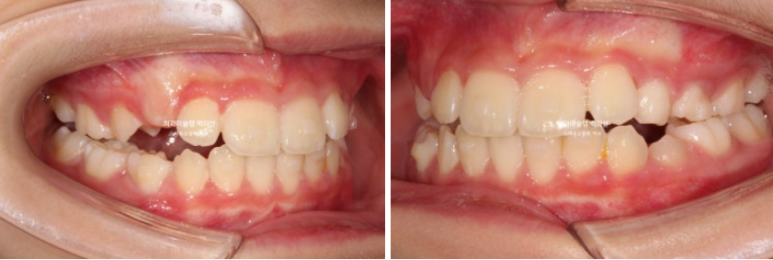

23.06~25.06

처음에 비해 무턱을 나타내는 수치가 6.4에서 4.7로 줄어들었습니다

4.7은 이 나이대에서는 정상범위 입니다.

2년간의 골격 변화를 중첩해보겠습니다

아래턱이 많이 자라나왔는데 하관 길어짐 없이 바람직한 성장이 일어났습니다.